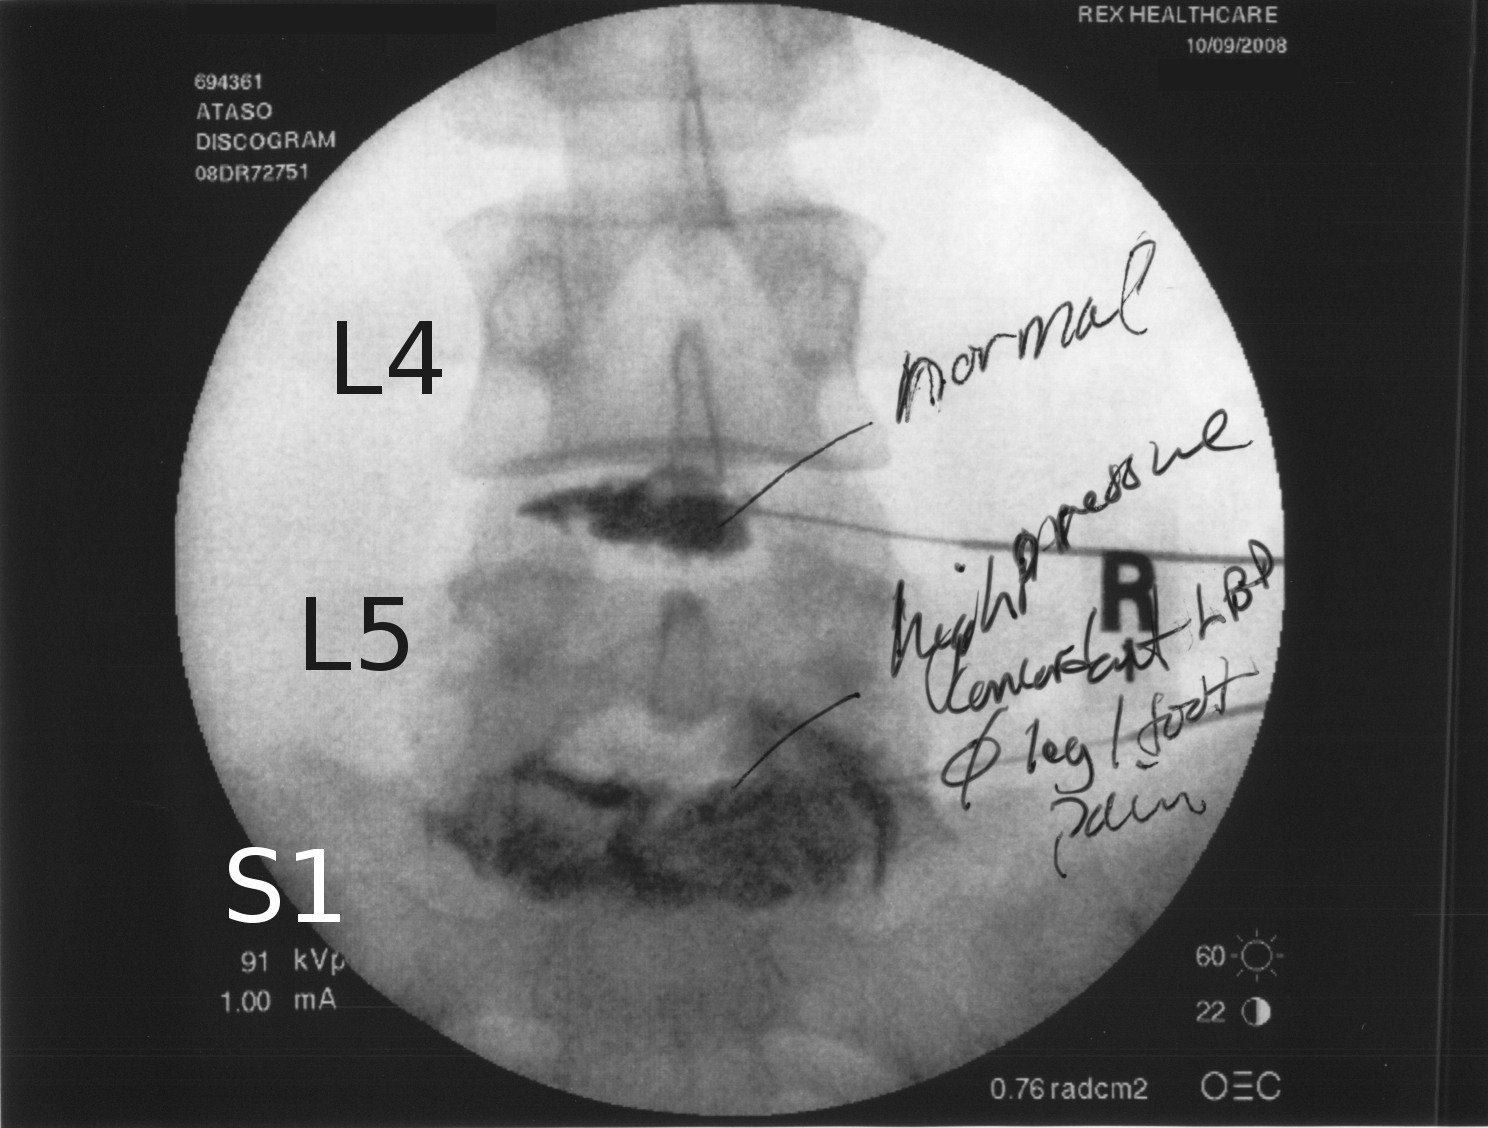

Discography after needle positioning during a L4L5 discectomy Discography Spine Procedure A discogram, also known as a discography, is a medical procedure used to diagnose the source of back pain. Discography or discogram for back pain and sciatica involves injecting a contrast agent into a disc suspected to be the cause of pain. The contrast agent increases the pressure within. During a discogram, a contrast dye is injected into the soft.. Discography Spine Procedure.